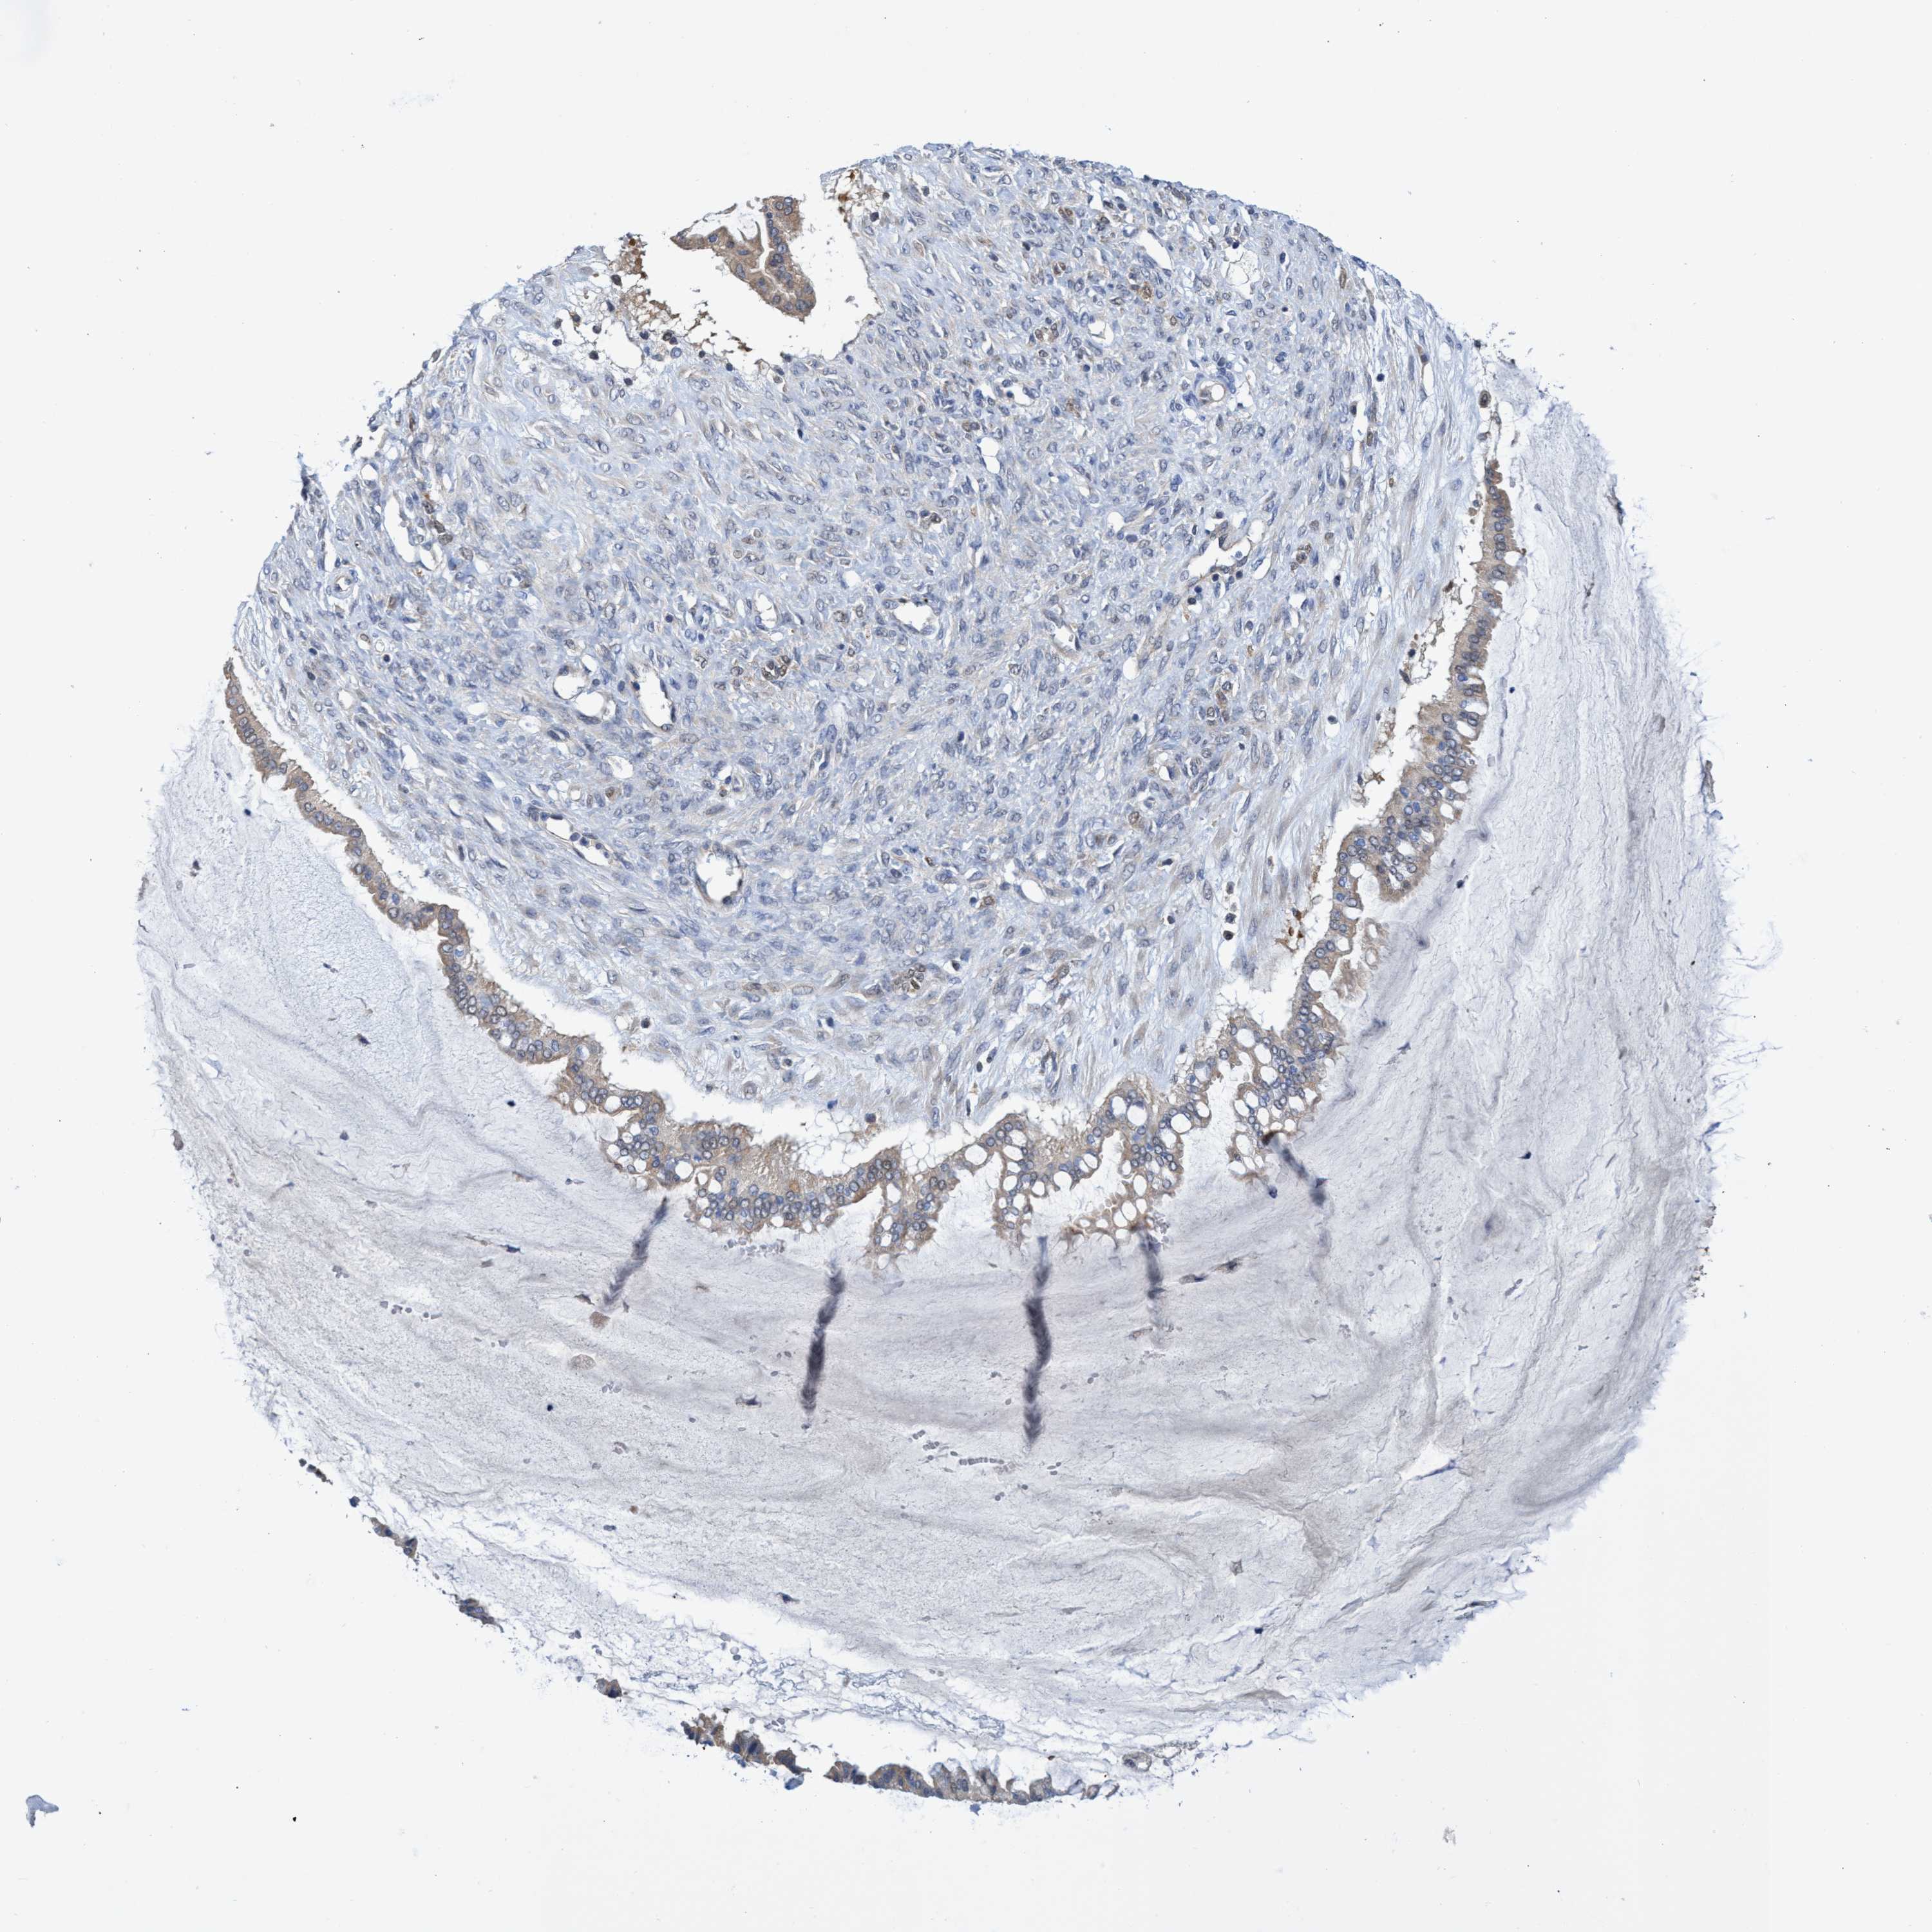

OVARIAN CANCER - Protein expressioni

A mouse-over function shows sample information and annotation data. Click on an image to view it in a full screen mode. Samples can be filtered based on level of antibody staining by selecting one or several of the following categories: high, medium, low and not detected. The assay and annotation is described here.

Note that samples used for immunohistochemistry by the Human Protein Atlas do not correspond to samples in the TCGA dataset.

Antibody stainingi

Antibody staining in the annotated cell types in the current human tissue is reported as not detected, low, medium, or high, based on conventional immunohistochemistry profiling in selected tissues. This score is based on the combination of the staining intensity and fraction of stained cells.

Each image is clickable and will lead to virtual microscopy that enables deeper exploration of all samples and also displays staining intensity scores, fraction scores and subcellular localization as well as patient and tissue information for each sample.

Antibody HPA023204

Antibody HPA027776

Staining

High

Medium

Low

Not detected

Intensity

Strong

Moderate

Weak

Negative

Quantity

>75%

75%-25%

<25%

None

Location

Nuclear

Cytoplasmic/membranous

Cytoplasmic/membranous,nuclear

Cystadenocarcinoma, serous, NOS

Carcinoma, endometroid

Cystadenocarcinoma, mucinous, NOS

Carcinoma, NOS